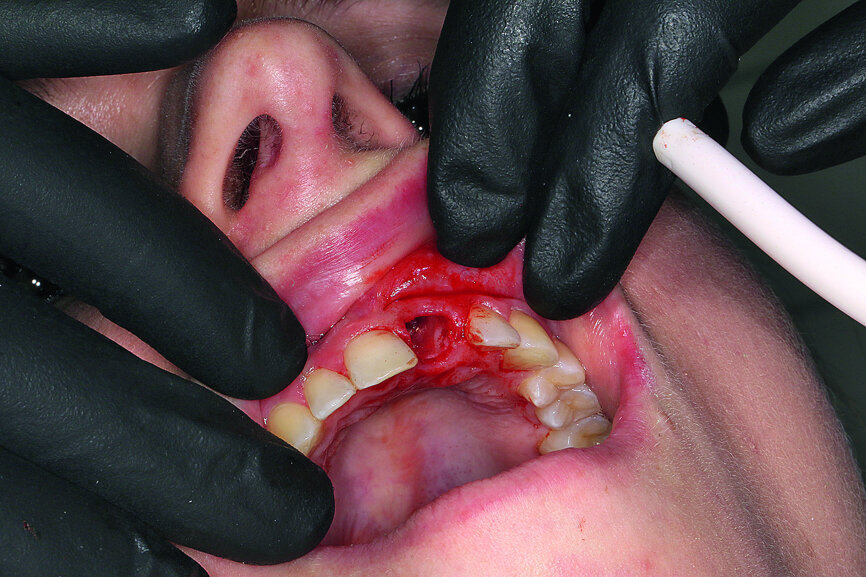

Fig. 7: Gentle extraction preserving the vestibular lamina.

Fig. 8: The resorption of tooth #21, external view. This confirmed the accuracy of the diagnosis from

the imaging procedure.

When extracting tooth #21, it was important to preserve the vestibular lamina to allow immediate implantation. For this reason, the Sharpey’s fibres were carefully severed with a periotome, and the tooth was gently removed (Fig. 7). The tooth had pronounced dentinal resorption, confirming the previously made diagnosis (Fig. 8). The SiroLaser Blue (Dentsply Sirona) with a wavelength of 970 nm was used to disinfect the alveolus. An OsseoSpeed EV 4.8–15 mm implant (Astra Tech Implant System, Dentsply Sirona) was inserted immediately using a surgical guide (SICAT OPTIGUIDE, SICAT; Fig. 9). At > 35 Ncm, sufficient primary stability was achieved.